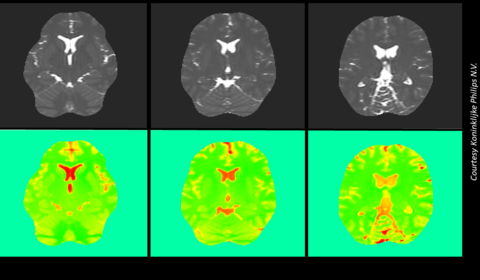

Quantifying the uncertainty of Electric Properties Tomography in medical imaging

Magnetic Resonance Imaging (MRI) is a diagnostic, mainly qualitative, technique used to visualise the soft tissues of a patient. The application of a strong magnetic field causes the protons in a patient’s hydrogen atoms to align with it. Radiofrequency pulses are then used to force the protons to move out of and back into alignment with the field,...

MRI standards spur innovation

Magnetic Resonance Imaging (MRI) is a diagnostic tool used to detect serious medical conditions, including cancers, heart disease and strokes. Thirty million MRI scans are performed in the EU each year providing doctors with valuable 3D images without the need for invasive investigations or patients being exposed to ionizing radiation. Increasingl...